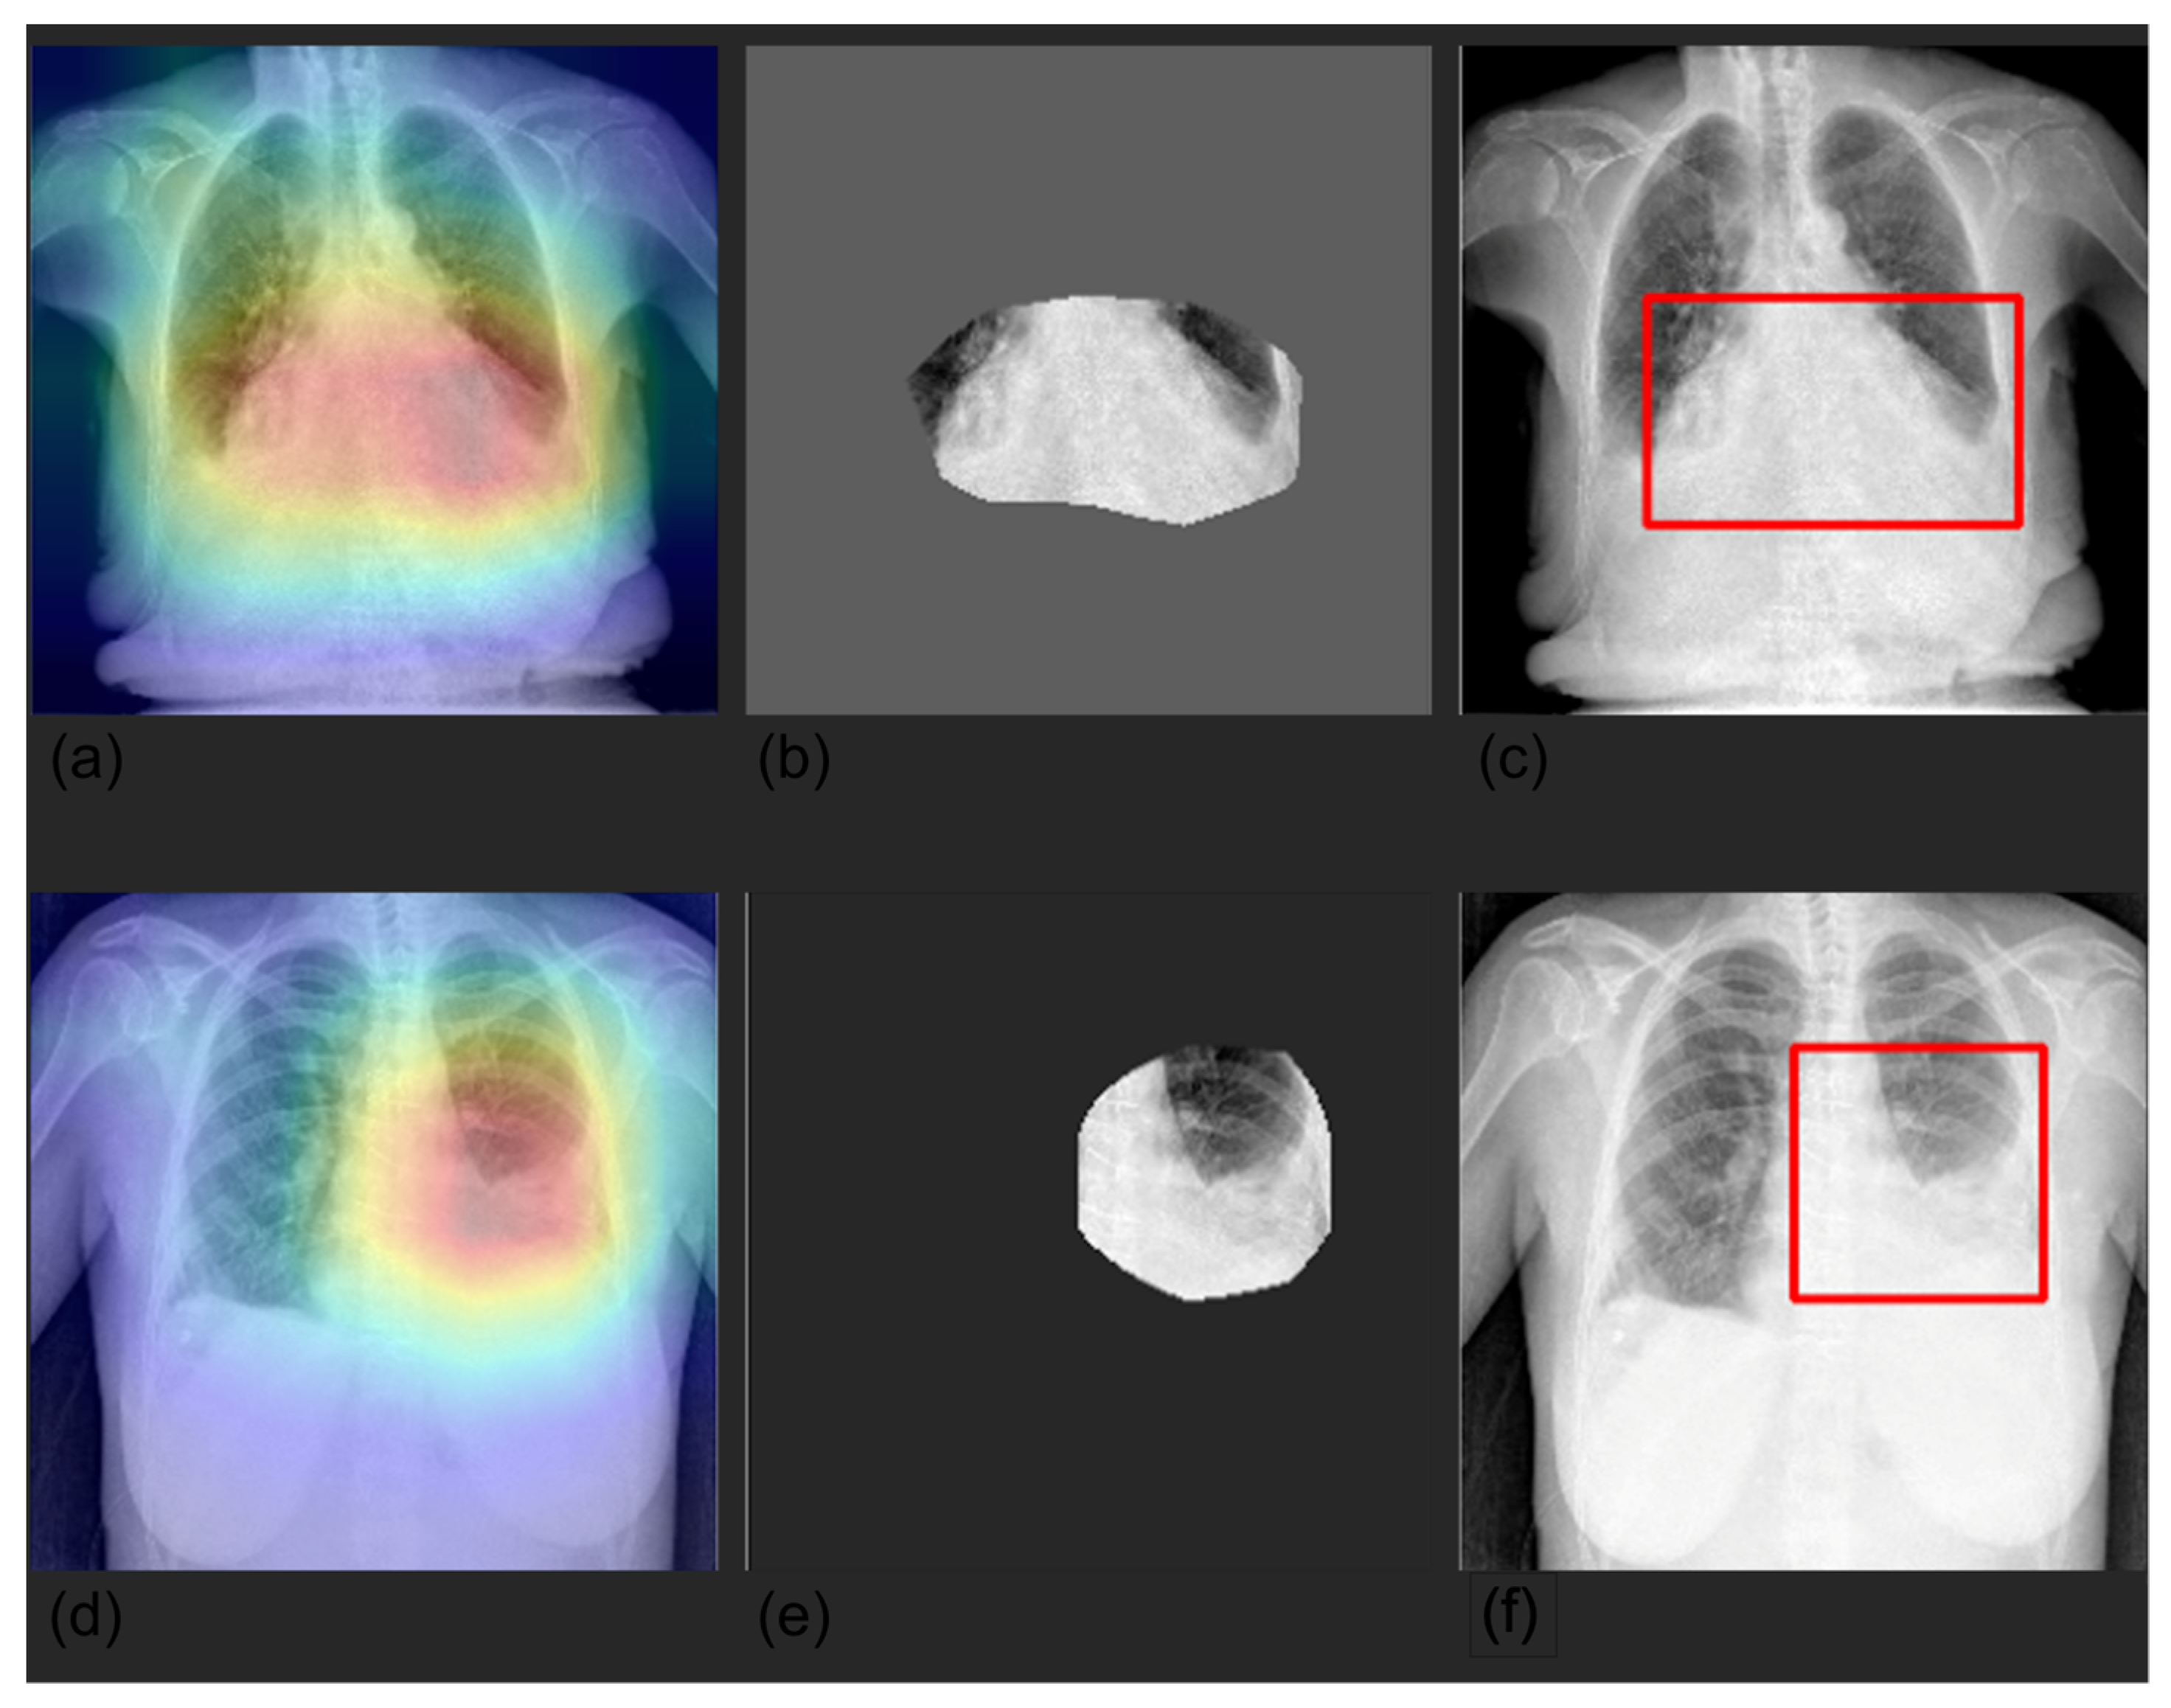

2.5. Explainability

3.4. Grad-CAM